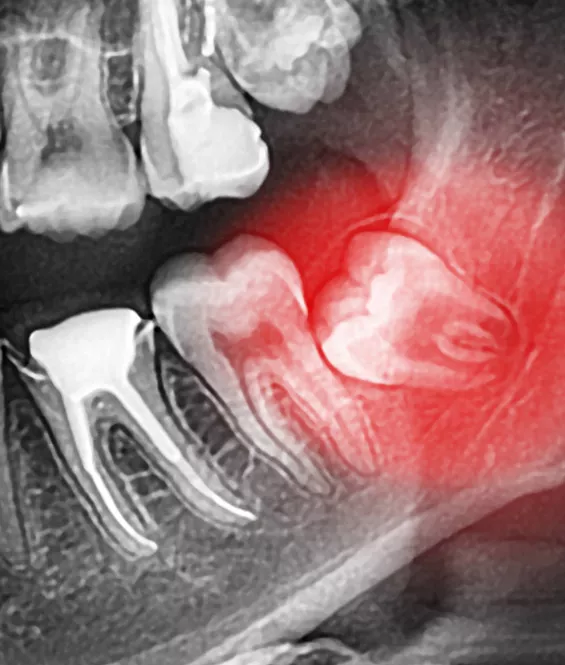

The wisdom teeth are a third set of large molars. They are usually the last of the adult teeth to grow in. For many patients, there is no room in the jaw for the wisdom teeth to emerge correctly, and they can become impacted or misaligned. If we detect that this is happening, we will recommend extraction of the wisdom teeth before they erupt through the gums.

Because the wisdom teeth are usually removed before they erupt, removal is usually a surgical procedure where the teeth are removed through incisions in the gums. The procedure is usually performed under local anesthetic and mild sedation. After the procedure, the incisions are closed with sutures.